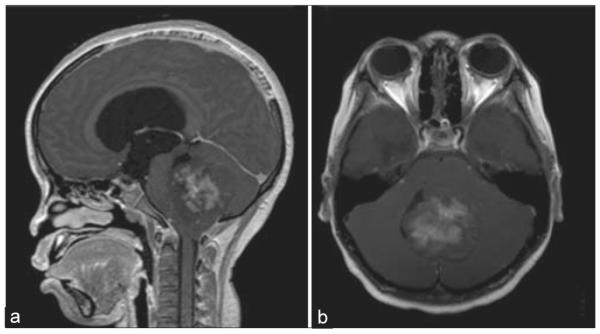

Materials and methods: Utilizing specimens from cases of pilocytic astrocytoma (n = 5), medulloblastoma (n = 5), and low-grade diffuse astrocytoma (n = 1), immunofluorescence were performed using primary antibodies against CD31, glial fibrillary acidic protein (GFAP), and aquaporin 4 (AQ4). Clinical, magnetic resonance imaging, operative, and histopathological findings were analyzed.

Results: Strongly-enhancing areas of medulloblastoma exhibited complete BBB breakdown with sparse GFAP and AQ4 staining around CD31-positive vessels. Moderately enhancing regions of pilocytic astrocytomas exhibited regions of intact BBB and vasculature surrounded by dense GFAP staining but reduced and disorganized AQ4 staining, suggesting tumor cells could not fulfill physiological BBB support. Non-enhancing low-grade diffuse astrocytoma demonstrated intact BBB with intense peri-microvasculature GFAP and AQ4 staining. AQ4 stained so strongly that AQ4 visualization alone delineated CD31-positive vessels.